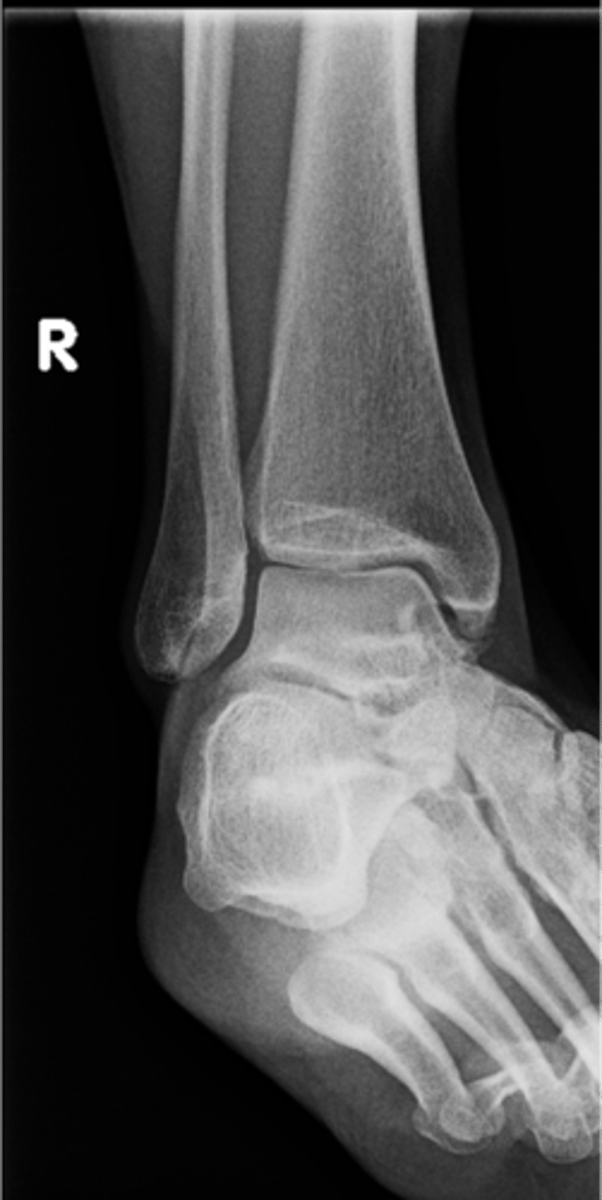

Right AP ankle

View?

<p>View?</p>

77

New cards

Lateral malleolus

ID 11

<p>ID 11</p>

78

Tibial plafond

ID 12

<p>ID 12</p>

79